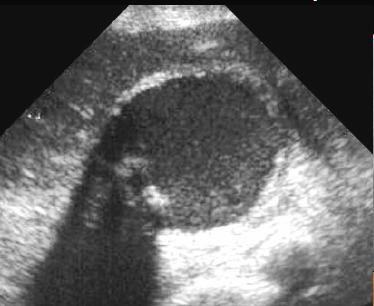

Cholecystite aigue

lithiasique : Images echographique de calcul

vesiculaire avec cone de hypoascoustique posterieure

. Distendue de la vesicule biliaire et epaissisement

de sa paroi . La contenue de la vesicule est

irreguliee . |